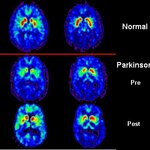

A Yeast Contribution For The Treatment Of Parkinson’s Disease

Scientists have just identified several molecules capable of reversing the brain abnormalities of Parkinson’s disease (PD), while also uncovering new clues for its origin in a study just published in the journal Disease Models and Mechanisms (1). PD is characterised by abnormal deposits of a brain protein called alpha-synuclein throughout the damaged brain regions, but exactly what they do there is not clear. The fact that their numbers and spreading are associated disease progression has made them, however, a major point of interest in PD research. The work now published suggests that these…